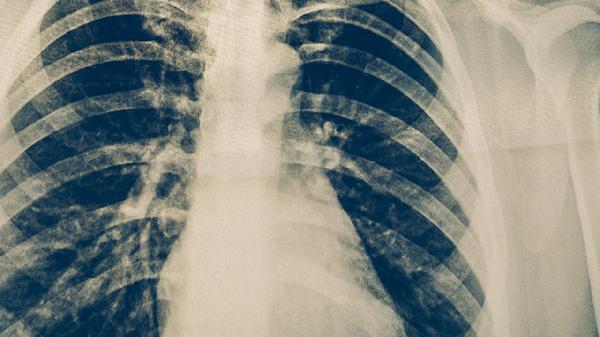

耐多药肺结核是指对异烟肼和利福平这两种一线抗结核药物同时产生耐药性的结核病。耐多药肺结核主要由不规范用药、药物敏感度不足、患者依从性差、基因突变、既往治疗失败等因素引起,临床表现为持续咳嗽、低热、咯血等症状,需通过药敏试验确诊并采用二线抗结核药物治疗。

耐多药肺结核患者应保持高蛋白饮食如鸡蛋、鱼肉,适量补充维生素A和D,避免吸烟及接触粉尘。每日开窗通风,咳嗽时掩住口鼻,用过的纸巾需焚烧处理。建议每3个月复查胸部CT和痰菌检查,密切监测需持续至疗程结束后2年。家属接触者应进行结核菌素试验筛查,必要时预防性用药。